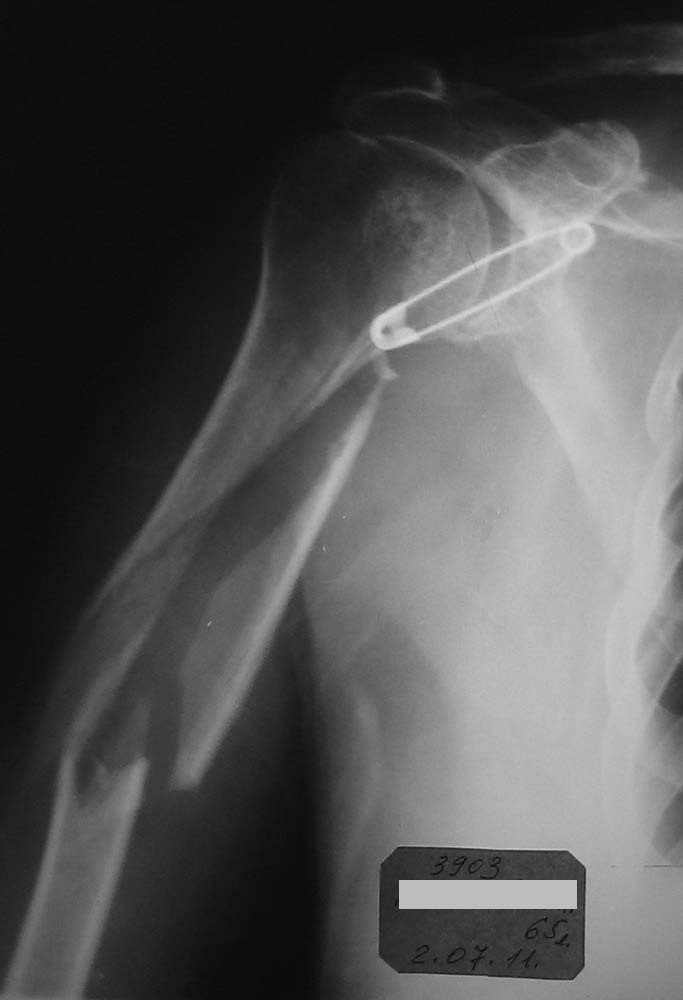

Хотелось бы увидеть снимки и руку на сегодняшний день. Причина проблем- неадекватный и нестабильный остеосинтез, осложнившийся остеомиелитом и несращением, и повторная травма тут ни при чем.

Оба предложенных варианта подходят, но важно увидеть длину оставшегося дистального отломка, состояние суставов.

Если первые две операции делали у Вас в клинике, то, пожалуйста, отправьте больную туда где ЭТО могут делать. Я уже говорил, что 65-ть для мировой ортиопедии не возраст...

Виктор! Начну с вопроса - что остановило первично заштифтовать, а не идти открыто? При такой установке пластины, Вы сразу дали шанс сломаться всему повторно. Если оставлять в аппарате, то срастаться будет лет так надцать (дефект около 10 см). Сохраните длину конечности и синтезируйте штифтом, ранняя нагрузка и штифт будет выполнять у Вас роль внутреннего эндопротеза и пусть срастается, главное будет рабочая рука, а не красивый рентген снимок.